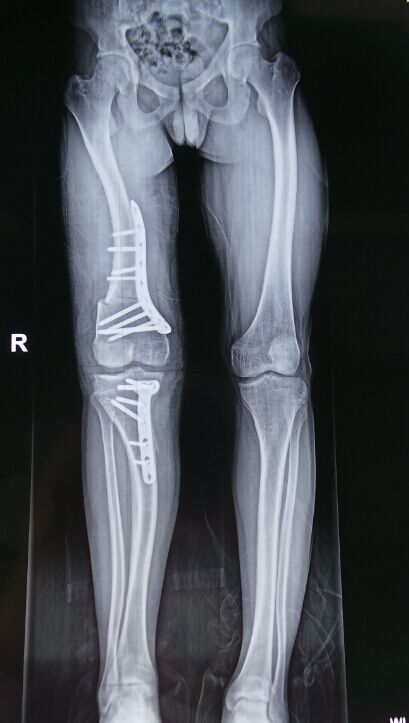

東望科技免費為右膝外翻畸形的患者打印模型,當患者看到自己的1:1腿骨模型的時候,才知道自己的病情是多么嚴重。

CT的平面二維數據不能夠準確的設計手術實施計劃,我們根據醫療影像數據打印出患者1:1腿骨模型, 醫生拿到模型后對患者的病灶“看得更清楚”,然后馬上進行手術設計,截骨角度尺寸等,都在模型上進行實際演練,最后設計出最終方案 。對3D打印并不了解的患者及其家屬看到模擬手術后,對手術的實施也更加放心了。

本來進行4-5個小時的手術,僅僅用了一個多小時就結束了。術后恢復相比于傳統手術,患者的恢復更快。